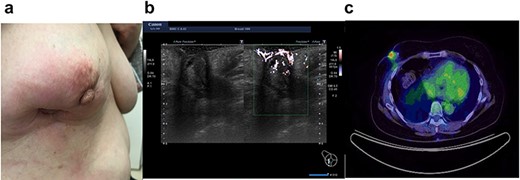

In 2014, a right breast tumor was located at the site of the surgical scar with slight erythema. Ultrasound revealed a hypoechoic mass with an irregular shape, indicating possible recurrence of breast cancer (Fig. 1a). Positron emission tomography–computed tomography (PET-CT) also suggested a right breast tumor with a relatively high standardized uptake value (SUV) and no distant metastasis (Fig. 1b). She underwent tumorectomy for both tumor removal and to obtain a pathological diagnosis, since she was afraid of false negative results with core needle biopsy (CNB). Pathological finding was a xanthogranulomatous lesion with cystic changes and dense sclerosis without any evidence of malignancy. There was no recurrence after surgery.

Ultrasound of the right breast in case 1 revealed a mass-like lesion 16.6 × 10.0 × 4.9 mm (a), and PET-CT showed that the right breast mass had an SUV max of 2.7 (b).